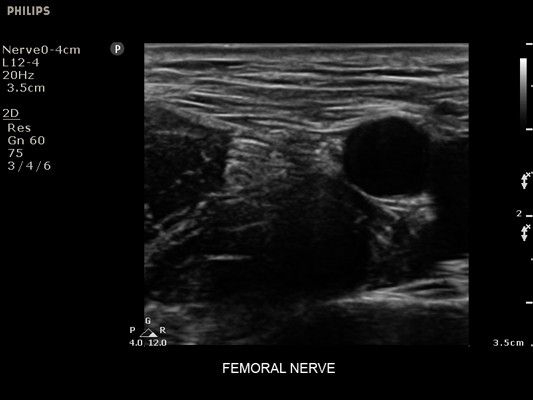

• Усиленная визуализация иглы без потери качества изображения окружающих тканей

• Метки центральной линии на датчиках L12-4 и C6-2 для упрощения внеплоскостной навигации

• Линейный УЗИ датчик Philips L12-4